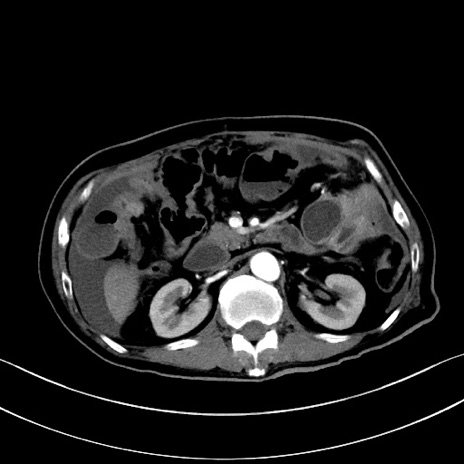

冠状断像

【症例】60歳代男性

【主訴】嘔吐

【現病歴】胃癌にて胃全摘後。食思不振が悪化し、夜中に嘔吐することがある。

【既往歴】胃癌、胃全摘、脾摘、胆摘後

【データ】WBC 5900、CRP 10.56